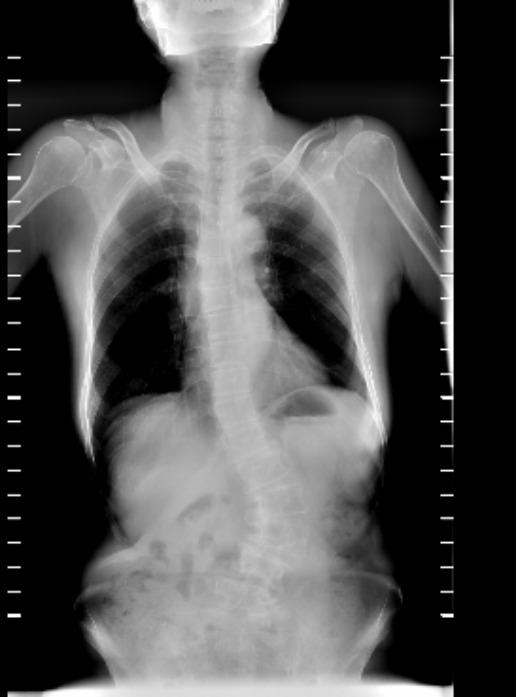

脊柱外科组(骨折、畸形、复杂融合固定)

脊柱畸形病历

主诉:腰部疼痛伴间歇性跛行10余年

现病史:患者10余年前无明显诱因出现腰部疼痛伴间歇性跛行,左侧较重,多于行走100米后症状加重,至当地医院诊治,考虑"腰椎间盘突出症"。给予药物对症治疗,膏药等,效果欠佳。今日为求进一步诊治,来我院椎间盘科,以“脊柱侧弯畸形,腰椎间盘突出症”为诊断收住我科。发病以来,神志清楚,精神尚可,饮食正常,睡眠一般,体力正常,大小便正常。

术前资料